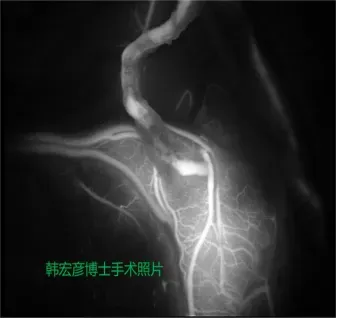

患者脑血管造影

术中荧光造影显示血管搭桥通畅